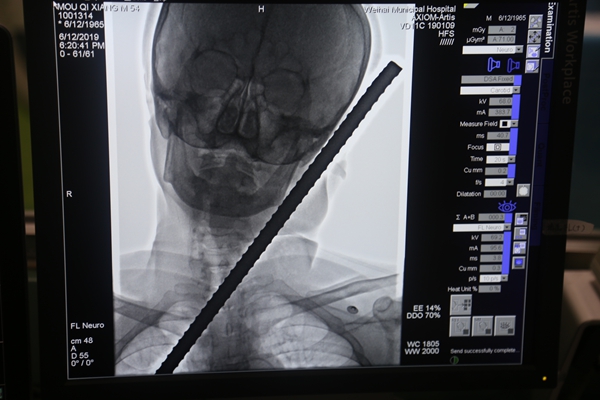

當日18時許,在市立醫院介入手術室,一名男子躺在大型設備上,正在進行造影檢查。一根螺紋鋼筋從他的下頜左側穿入后從左耳旁刺出,在扎入和刺出部位都裸露著表面帶有鐵銹的鋼筋頭,還有滲血并伴血凝塊形成。

此時,在介入手術室外間,來自口腔、介入放射、耳鼻咽喉頭頸外科等科室的專家正圍在電腦前,面色凝重地盯著電腦顯示屏顯示的各個角度的3D圖像,仔細查看著插入男子面部的鋼筋走向、所傷及的部位等。

“鋼筋自下頜升支后緣,下頜后窩處穿入,頸動脈只有顳淺動脈斷裂,外耳道有損傷。”隨著檢查結果出爐,現場的緊張氣氛一下子得到了緩解,專家們也稍微松了口氣:“傷者實在太幸運了,雖然有一些損傷,但鋼筋在進入體內時巧妙地避開了面神經總干、頸動脈等重要部位,算是躲過了一劫。”根據檢查情況,專家進行了分析評估。隨后,對于斷裂的顳淺動脈,立即進行了栓塞止血處理。